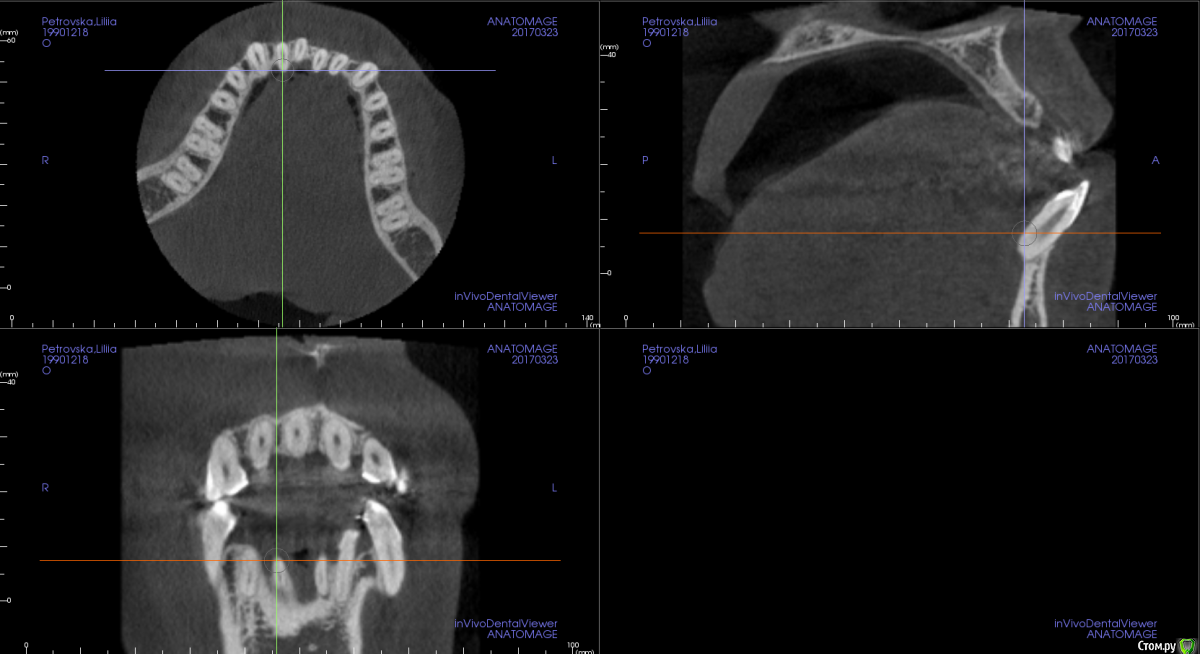

m.d.n Опубликовано 20 марта, 2017 Поделиться Опубликовано 20 марта, 2017 срезы кт покажите . на чем остановились Ссылка на комментарий

Opdihatop Опубликовано 26 марта, 2017 Автор Поделиться Опубликовано 26 марта, 2017 Прошу:313233414243 Ссылка на комментарий

Opdihatop Опубликовано 4 марта, 2017 Поделиться Опубликовано 4 марта, 2017 И снова здравствуйте, коллеги. Вот такой вот случай к рассмотрению. Много лет назад пациентка уже проходила "камуфляжное" лечение. Со слов пациентки оно было закончено с передним открытым прикусом. Сейчас ситуация такая. Пациентка думает над ортохирургией, но меня смущает фронт н/ч. И по снимкам и по ситуации во рту корни 32, 31, 42, 43 зубов фенестрировали лингвальную кортикалку почти на всем протяжении, 33 - вестибулярную. Вопрос вот в чем: что делатьс этими зубами? Возможно ли их поставить на место? Или лучше не трогать, дольше простоят? Ссылка на комментарий